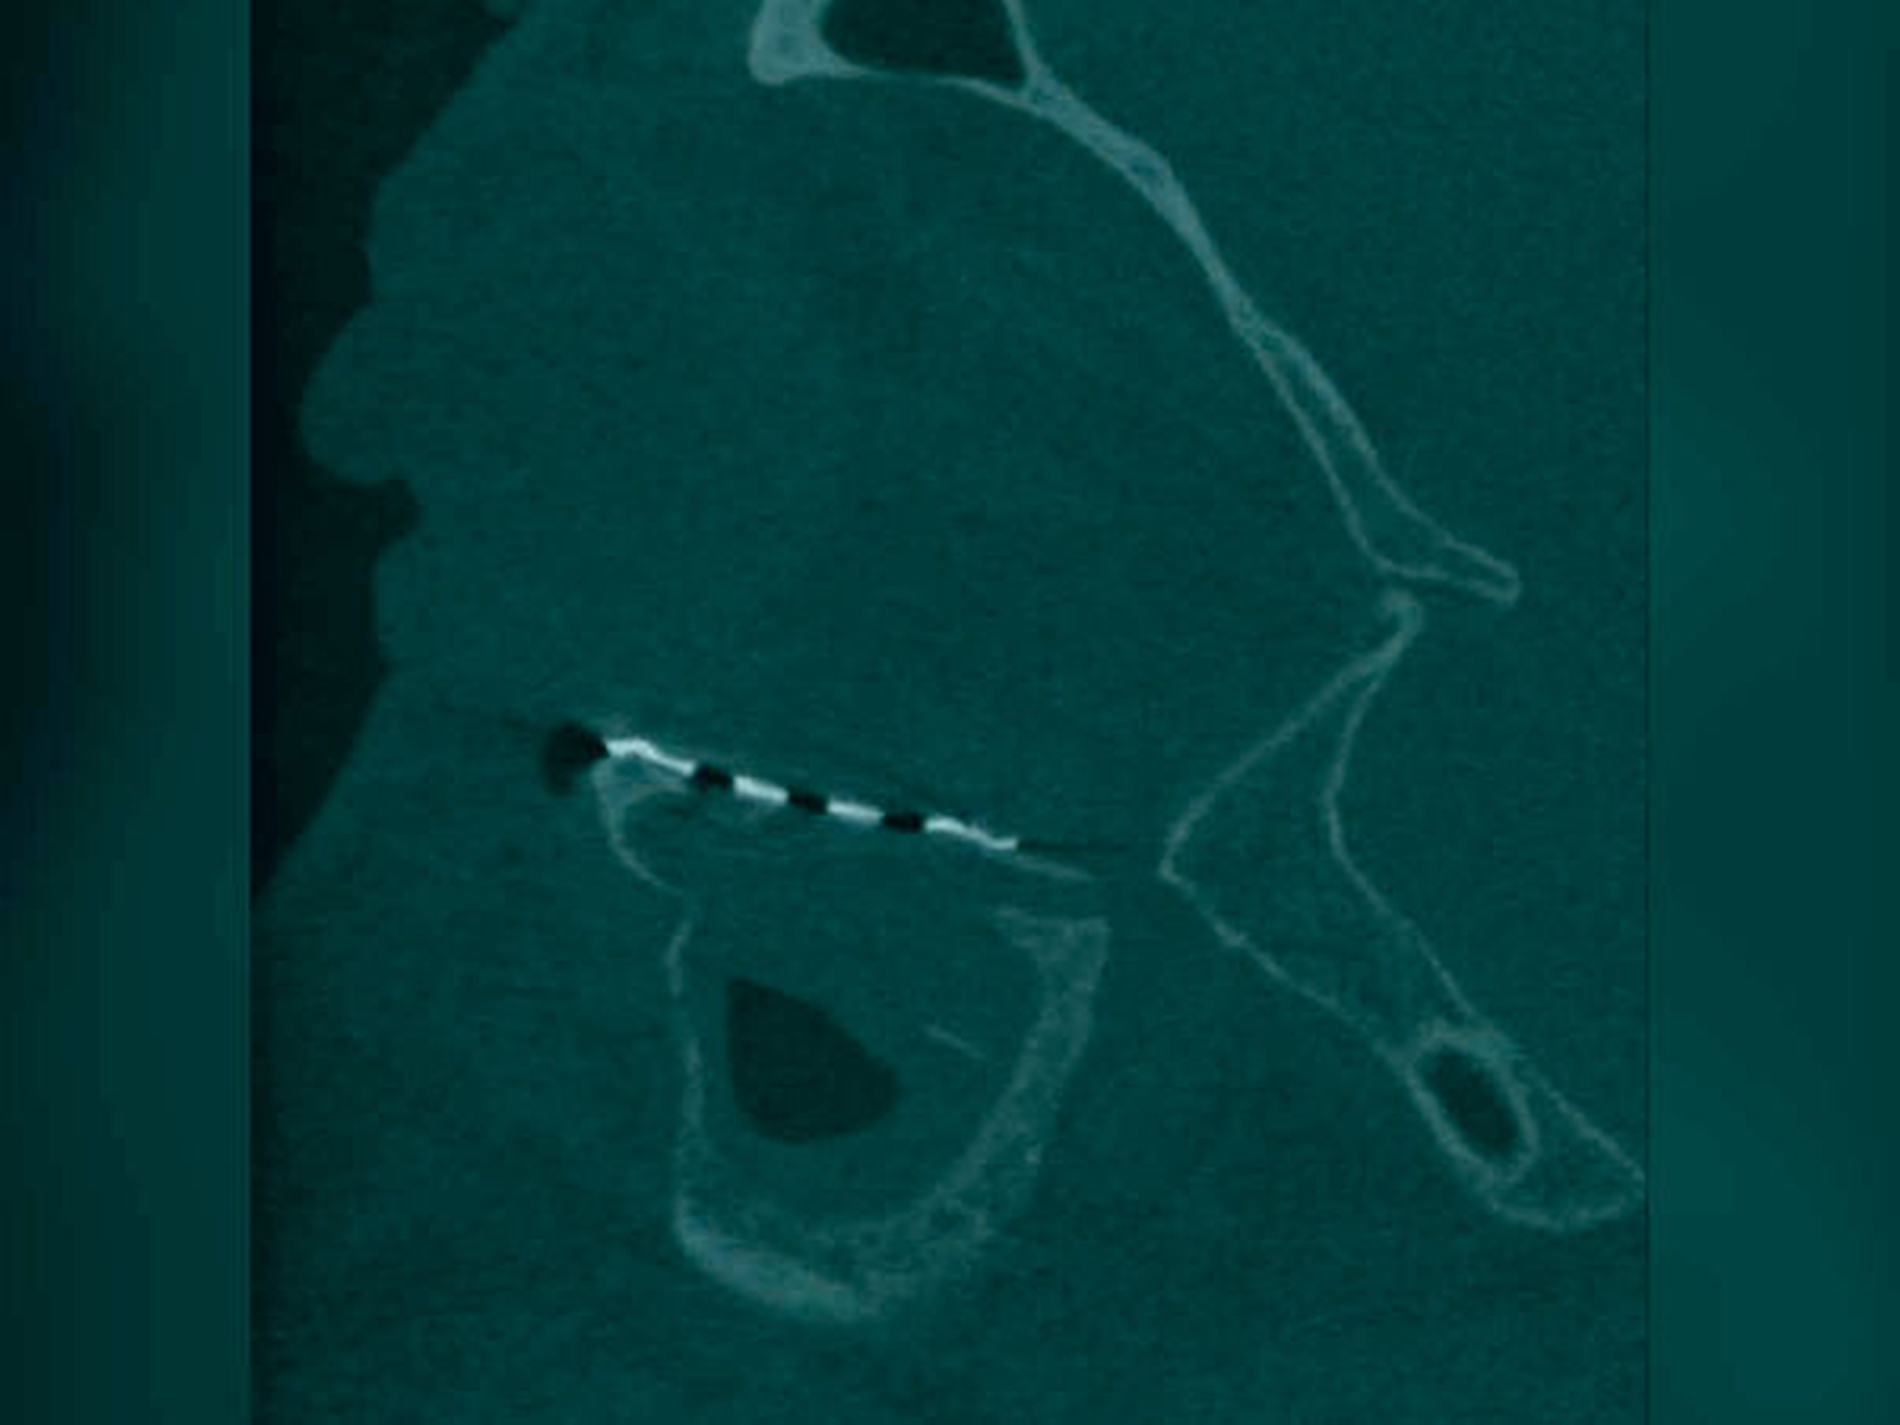

Anhand einer präoperativ durchgeführten Dünnschicht-CT kann im Anschluss gemeinsam mit dem Hersteller (KLS Martin Group, Tuttlingen) im volldigitalen Workflow (IPS CaseDesigner®) eine präzise Planung und die Anfertigung des patientenindividuellen Orbitameshs (Abbildung 3) erfolgen. Zur Rekonstruktionsplanung wird der gesunde, nicht verletzte Orbitaring digital basierend auf den oben genannten CT-Daten auf die frakturierte Seite gespiegelt. Das so generierte PSI zur Rekonstruktion des dislozierten Orbitabodens und ausgesprengter medialer Orbitaanteile wird anschließend komplikationslos unter navigationsgestützter Kontrolle über einen transkonjuktivalen Zugang in Intubationsnarkose eingebracht und unter Schonung des N. infraorbitalis mit drei Osteosyntheseschrauben verankert (Abbildung 4). Die postoperativ erfolgte, dreidimensionale Bildgebung mittels digitaler Volumentomografie (DVT) zur Lagekontrolle des PSI zeigt eine regelhafte Position mit suffizienter Anlagefläche sowohl kaudal als auch medial (Abbildungen 5 und 6).